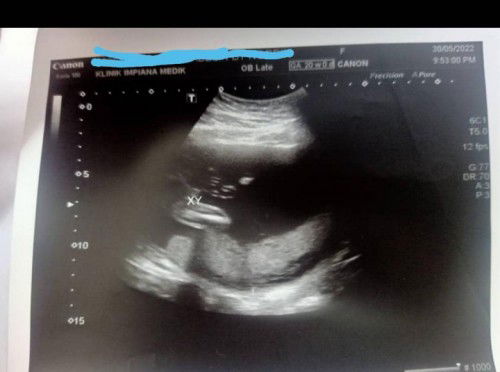

Ini baby apa ya? Dr. cakap boy... agak2 mommy semua ni boy ke girl ye?

BOY OR GIRL? #ingintahu #firstbaby #pleasehelp